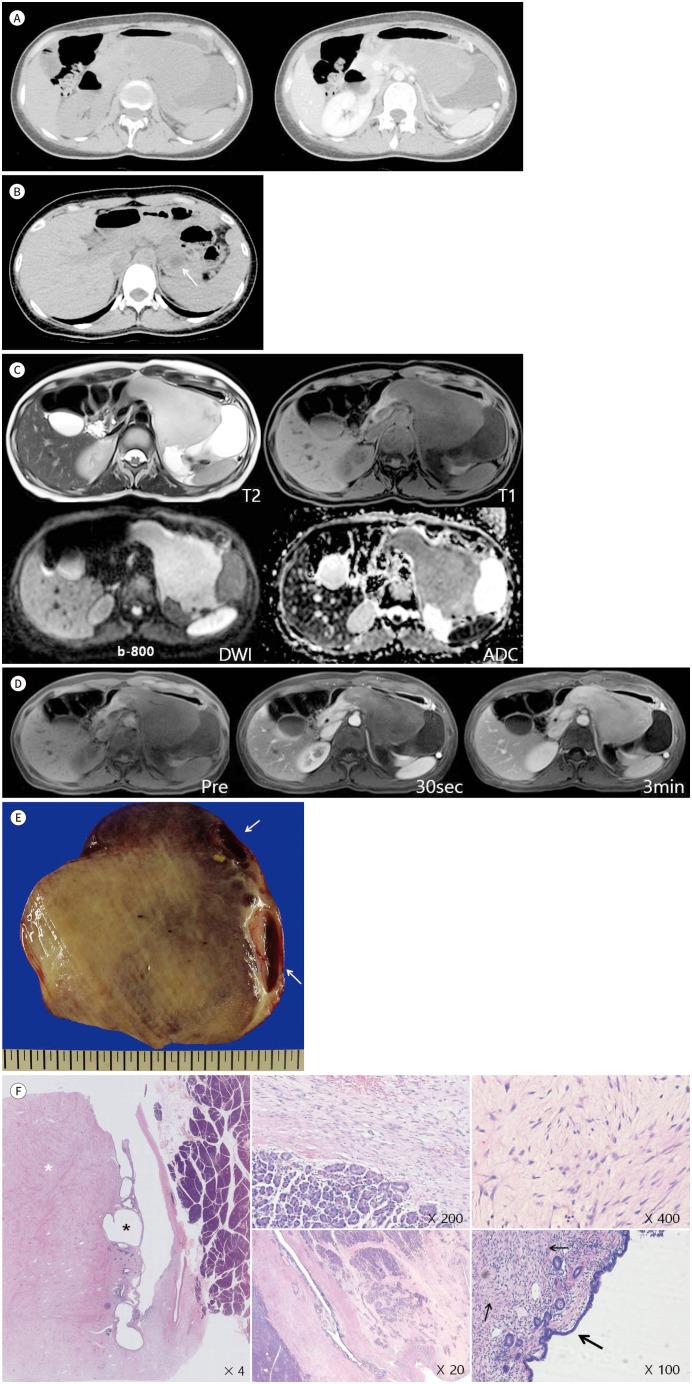

Pancreatic collision tumors are rare neoplasm, and cases consisting of ductal adenocarcinoma with a neuroendocrine tumor, intraductal papillary mucinous neoplasm with a neuroendocrine tumor, and solid pseudopapillary neoplasm with a neuroendocrine tumor have been reported. We report a case of a rapidly growing pancreatic collision tumor consisting of desmoidtype fibromatosis and mucinous cystic neoplasm in a 30-year-old pregnant female. To the best of our knowledge, this is the first reported case of a pancreatic collision tumor consisting of desmoid-type fibromatosis and mucinous cystic neoplasm.

胰腺碰撞瘤是一种罕见的肿瘤,由导管腺癌合并神经内分泌肿瘤、导管内乳头状黏液性肿瘤合并神经内分泌肿瘤以及实性假乳头状肿瘤合并神经内分泌肿瘤组成的病例已有报道。我们报告一例30岁怀孕女性的胰腺碰撞瘤,该肿瘤由硬纤维瘤样纤维瘤病和黏液性囊性肿瘤组成,生长迅速。据我们所知,这是首例由硬纤维瘤样纤维瘤病和黏液性囊性肿瘤组成的胰腺碰撞瘤病例。